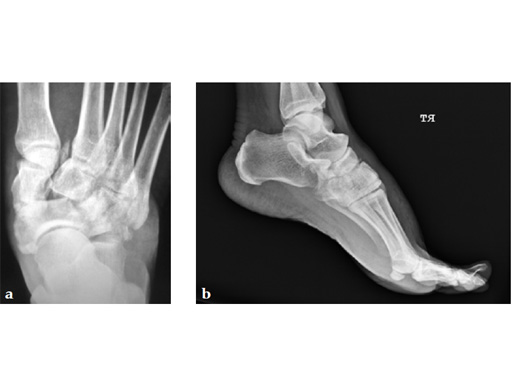

A 38-year-old man fell from a 7-foot height while at work. The patient was seen at an urgent care facility and diagnosed with an ankle sprain. He was placed in a stirrup brace and instructed to bear weight as tolerated.

Case provided by Michael Castro, Scottsdale, Arizona

After 4 months the patient presented for a second opinion. His complaint was pain to the lateral column and subtalar joint. The preoperative lateral x-ray is notable for a malunited talar neck fracture with subluxation of the subtalar joint. The disproportion of the medial and lateral columns and a cavovarus position of the foot are seen on both the AP and lateral views. The degenerative changes at both the talonavicular and subtalar joints are significant.